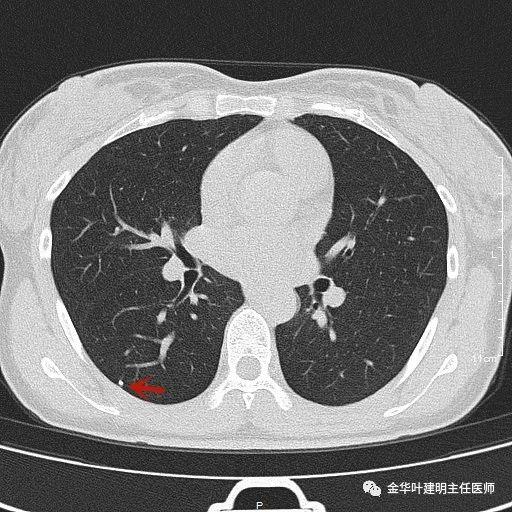

叶建明谈结节:检查发现肺实性结节怎么办?个人版实用指南

上图示浸润性腺癌典型表现。实性结节,有细毛刺征,有血管进入病灶,部分地方有浅分叶。